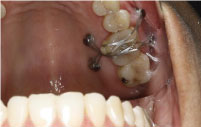

Four Dewimed MOSAS micro screws were placed, two on the buccal (7 mm long/1.3 diameter) and two on the hard palate (9 mm long/1.3 diameter) in relation to tooth 1.6. The exact site was determined after studying the cone-beam and where it would be most effective to intrude the molar.

To replace tooth 4.6 a BioHorizons Cylindrical Tapered Internal 4.6 × 12 mm. implant was chosen (Figure 2).

Figure 2: Installed vestibular TADs. View Figure 2